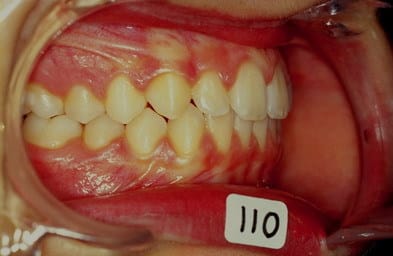

cas n 2

QH + Ecran cuccal pendant 4 mois seulement separent les photos